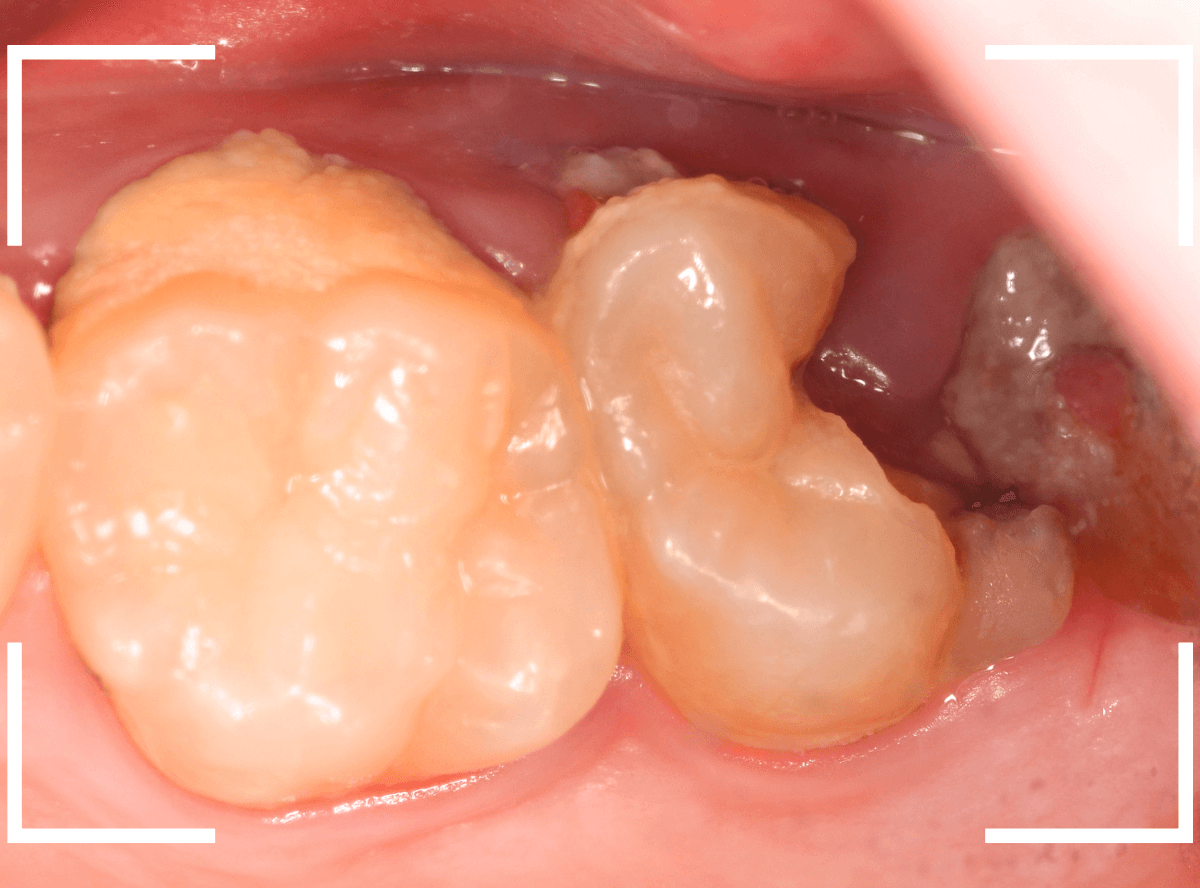

お口の中を確認すると、上の奥歯がひどい虫歯です。

その奥のおやしらずは歯の残骸が残っている状態です。

手前の歯も、大量の歯石がついています。

今回は、痛みもなく、見た目にはまだ治療で何とかなりそうに見えるケースです。

大きな虫歯なのはわかりますが、治療で何とかなりそうにも見えます。